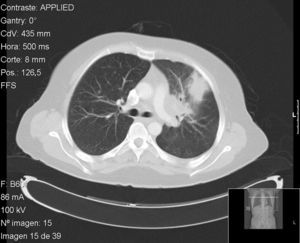

Case no. 1: The patient was a 41-year-old HLA-B27-positive woman diagnosed, at the age of 30 years, as having ankylosing spondylitis affecting the axial skeleton and recurrent acute anterior uveitis. Her response to nonsteroid anti-inflammatory drugs (NSAID) was suboptimal and treatment with adalimumab was begun in 2006, following screening for TB (at the time of the Mantoux test, she was only being treated with NSAID). In 2009, after 35 months of adalimumab, she presented with fever, dry cough, odynophagia, and headache, and was feeling generally unwell. Pulmonary computed tomography revealed a mass measuring 4cm in the anterior segment of left upper lobe, with suprahilar and prevascular adenopathy (Fig. 1). On this occasion, she reacted to the Mantoux test with an induration measuring 20mm 48h later. Fiberoptic bronchoscopy was performed with transbronchial biopsy and the study of the specimen revealed a mucosa with chronic granulomatous inflammation plus necrosis, and the culture was positive for Mycobacterium tuberculosis. After tuberculostatic therapy with rifampicin, pyrazinamide and isoniazid, the patient's disease resolved.